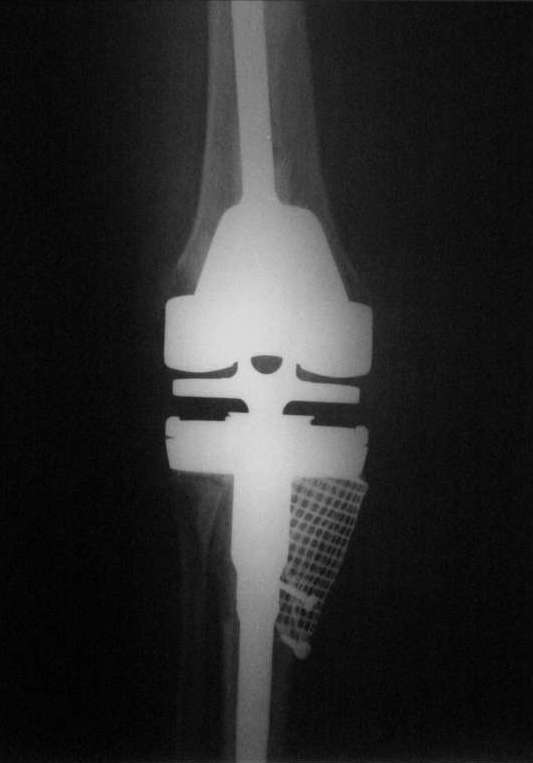

Вот то, что получилось и снимки во время операции.С уважением, Римашевский Д.

Как я уже писал ранее, пациентке до этого дважды устанавливались первичные протезы, выполнялась лавсанопластика внутренней коллатеральной связки.

Уже при первичном эндопротезировании большеберцовая кость была резецирована на 0.5 см. ниже головки малоберцовой кости с существенным варусом.

При ревизии с установкой второго протеза (обычного PS) ситуация ухудшилась еще в еще большей степени + ножка тибиального компонента пробила наружный кортикал большеберцовой кости.

Вдобавок ко всему все это ещё и нагноилось.

Пациентка обратилась к моему хорошему знакомому.

Мы посоветовались и решили удалить все и поставить спейсер на 3- 4 месяца, провести курс антибиотиков.

После установки спейсера рана зажила хорошо.

От артродеза пациентка отказалась и мы рассматривали 2 варианта:

1) Установить онкологический протез GMRS Stryker с резекцией проксимального конца большеберцовой кости.

2) Установить простой hinge MRH Stryker с костной пластикой дефекта.

Мы предпочли второй вариант. (Отдельное спасибо А.В. Каминскому за интересную статью).

Примерно через 4 месяца после установки спейсера мы пошли на ревизию.

После открытия сустава оказалось, что головка малоберцовой кости возвышается над наружным кортикалом большеберцовой кости на 1 см, а над разрушенным внутренним мыщелком на 3 см (см. фото).

Рассверлили канал большеберцовой кости. В канал поставили стержень. По нему, на наружный кортикал посадили шаблон тибиального компонента (см. фото). Определили размер дефекта внутреннего мыщелка, который надо закрыть сеткой.

На внутренний мышелок установили сетку из нержавеющей стали Ex-Change Stryker (предназначенную для укрепления верхнего края вертлужной впадины) и фиксировали её 4 винтами. Подрезали сетку сверху по шаблону тибиального компонента. После этого рассверлили канал б/б и бедренной костей под протез. Используя систему пульс-лаважа Stryker SurgiLav c насадкой - щеткой для промывания каналов промыли бедренную и большеберцовую кости. Последнее сверло, которым рассверливали проксимальную часть канала б/б кости, оставили на месте. Аллотрансплантат перемололи на костной мельнице, перемешали с 3 гр. ванкомицина и достаточно плотно заполнили им дефект внутреннего мыщелка, утрамбовывая импактором костную стружку в единую массу.

Так как наружный кортикал был на 1.3 см. ниже головки малоберцовой кости, пришлось использовать вставку под большеберцовый компонент 1 см. На цемент c ванкомицином поставили тибиальный компонент с ножкой 11/80 мм.

Бедро по шаблону резецировали (лучше сказать «причесали»). Системой пульс-лаваж с щеткой для отмывания костной поверхности основательно все отмыли и поставили на цемент бедренный компонент c ножкой 11/155 мм.